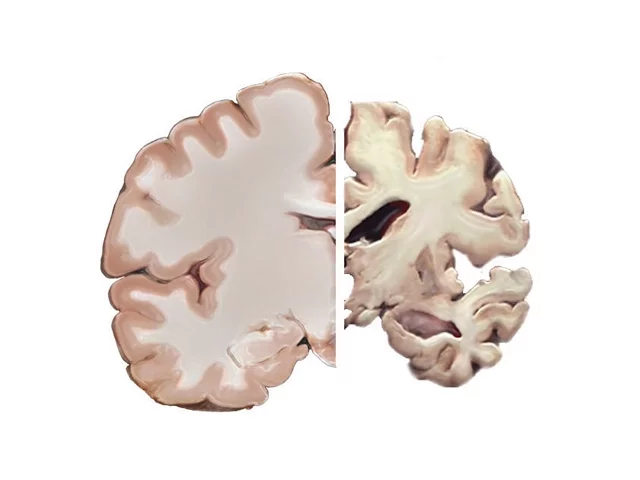

dementia cases are Alzheimer's the disease is associated with the accumulation of plaques and tangles in the brain changes accompanied by damage to brain cells and their death the older a person is the more likely they are to have developed Alzheimer's but Alzheimer's is not a part of normal aging symptoms of Alzheimer's disease include a decrease in the ability to think and remember confusion about time and place new difficulties speaking and writing changes in mood and personality as we fight against other diseases and live longer lives Alzheimer's looms on the horizon as if waiting for us

deaths what we do know is that Alzheimer's disease is associated with these plaques in the brain as well as another protein related anomaly tangles a protein called tau stabilizes microtubules in brain cells like railroad ties holding tracks together the tracks that guide nutrients and other molecules throughout the cell in many neurodegenerative diseases tau proteins become abnormally sticky and tangled with other tau proteins compromising the delivery network we do know some factors associated with increased or decreased risk but their exact relationships with cognitive decline aren't all certain things associated with a reduced risk for Alzheimer's disease